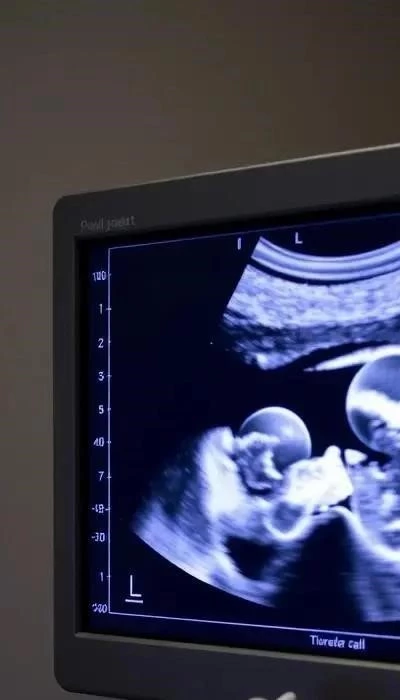

ХГЧ (хорионический гонадотропин человека) – это гормон, который вырабатывается плацентой сразу после имплантации оплодотворенной яйцеклетки. Анализ крови на ХГЧ является одним из самых точных и ранних методов подтверждения беременности.

Анализ проводится в лаборатории путем взятия венозной крови. Он позволяет определить наличие ХГЧ даже до задержки менструации, что делает его особенно полезным для ранней диагностики. Согласно данным из Экономико-правовой газеты Норма, нормы ХГЧ динамически меняются в зависимости от срока беременности.

Повышенный уровень ХГЧ указывает на беременность, а его количество удваивается каждые 48-72 часа в первые недели. Отклонения от нормы могут свидетельствовать о различных состояниях, включая внематочную беременность, многоплодную беременность или угрозу выкидыша. Важно помнить, что интерпретацию результатов должен проводить врач.